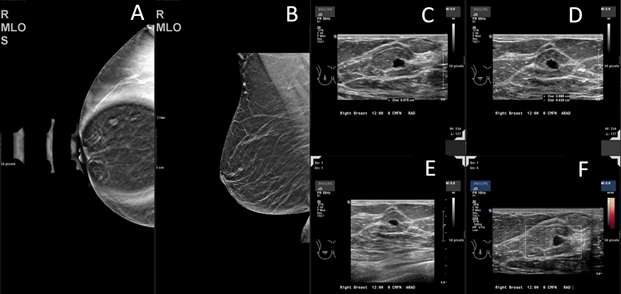

Biopsy proven breast metastasis from retroperitoneal leiomyosarcoma with additional metastasis to the liver and lungs:

Case: Metastasis to the Breast From a Non-breast Primary Cancer Figure 4

Figure 4: (A) On a MLO mammogram image, there is an isodense round mass with circumscribed margins, at 12 o'clock posteriorly at a distance of 12 cm from the nipple. (B-D) On ultrasound images, there is a solid mass at the site of the mammographic mass at 12 o'clock posteriorly. The characteristics of the finding include hypoechoic echo pattern, circumscribed margins and a round shape. Vascularity is present immediately adjacent to the lesion. (E) CT chest image demonstrates a 12 mm, right breast mass.